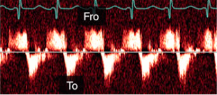

Flying w sign

What is seen in the m-mode image?

What diagnosis is consistent with this spectral Doppler?

What sign is seen?